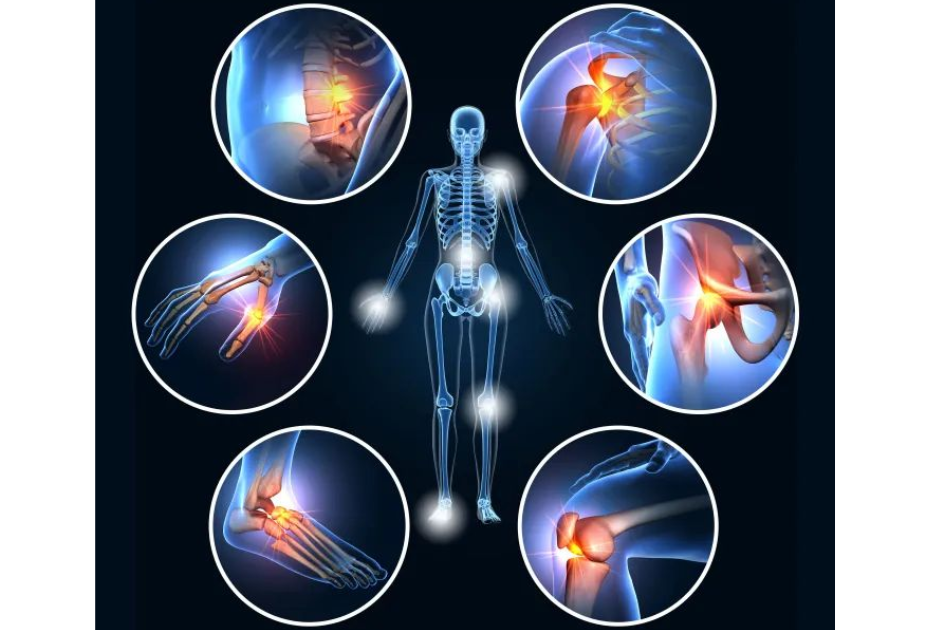

Rehabilitation after an injury, surgery, or chronic pain can be tough physically and mentally. This is where General Physical Therapy plays a role — a critical component of contemporary orthopaedic care that assists patients in regaining strength, mobility, and function.

Whether it’s a sports injury, joint ache, or post-surgical rehabilitation, physical therapy works to enhance movement, minimize pain, and avoid further complications. Patients at the Centre for Orthopaedic Care in Pune receive skilled orthopaedic care and scientifically formulated rehabilitation programs to ensure a safe and confident return to active life.

Ailments Usually Treated with Physical Therapy

Physical therapy benefits individuals across all ages and activity levels. In orthopaedic clinics in Pune, it is commonly used to treat:

- Joint and Muscle Pain

Conditions like arthritis, frozen shoulder, or muscle strain can be effectively managed with focused therapy. - Post-Surgical Rehabilitation

Following orthopaedic procedures such as joint replacement, ligament repair, or spine surgery, therapy ensures safe and faster recovery. - Sports Injuries

Athletes recovering from sprains, ACL injuries, or tendon damage require specialized physical therapy to regain strength and flexibility. - Back and Neck Pain

Caused by poor posture, sedentary habits, or disc problems — physiotherapy restores movement and minimizes stiffness. - Fracture Recovery

Once a cast or immobilizer is removed, physical therapy helps rebuild strength and restore normal movement.